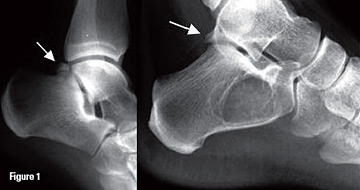

MRI of the ankle can demonstrate bone marrow edema within the os trigonum and at synchondrosis with the posterior talar tubercle, which is considered a reliable sign of PAIS.1,5 Other common sites of edema include the posterior talus and the posterior calcaneus. MRI can demonstrate fractures, if present, through the os trigonum that are difficult to evaluate with plain films.

The additional inflammatory changes in the adjacent soft tissues can also be demonstrated on MRI, including edema or enhancement of posterior soft tissue, indicating posterior tibiotalar joint synovitis caused by the repetitive compression and posterior-capsular thickening. There can be fluid around the flexor hallucis longus (FHL) tendon or synovial enhancement, which is caused by tenosynovitis of the FHL and high signal changes and/or enhancement within the musculotendinous junction of FHL muscle belly due to impingement.5-6